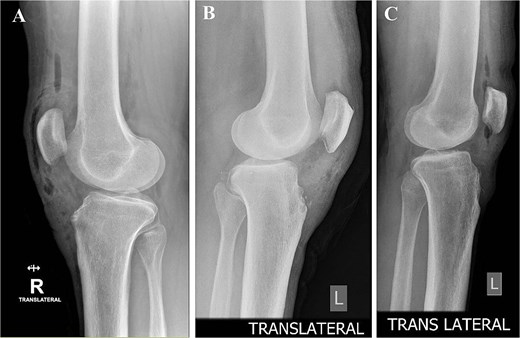

On physical exam, they had localized tenderness at the tibial tubercle, pain when kneeling, and discomfort with resisted knee extension. X-rays showed persistent ossicles in all cases, and we followed up with MRI to rule out any other underlying issues (Fig. 1).

Preoperative lateral radiographs showing persistent tibial tubercle ossicles. (A) Right knee for first case. (B) Left knee for second case. (C) Left knee for third case.